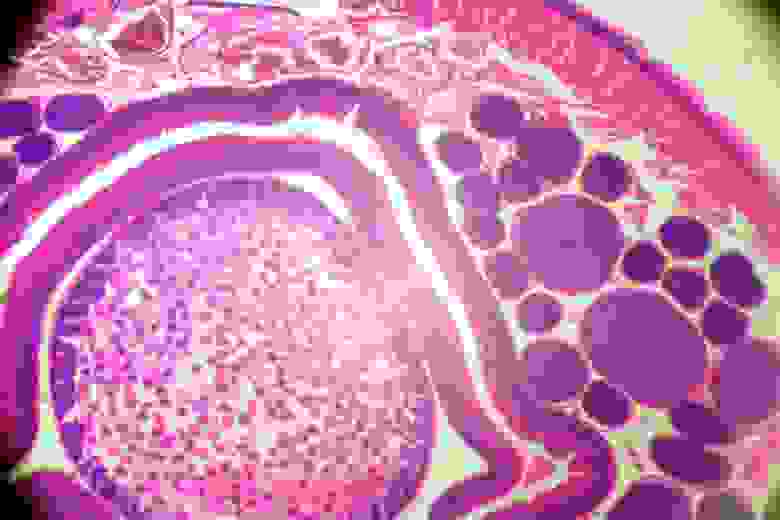

На фотографии поперечный разрез аскариды.

На фотографиях получается засветка центра в связи с тем, что зеркало в микроскопе вогнутое.